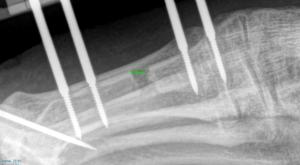

Neglected transscaphoid perilunate fracture dislocation

CASE REPORT Neglected transscaphoid perilunate fracture dislocation treatment